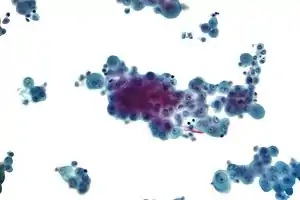

Imaging

Diagnosing mesothelioma is often difficult because the symptoms are similar to those of a number of other conditions. Diagnosis begins with a review of the patient's medical history. A history of exposure to asbestos may increase clinical suspicion for mesothelioma. A physical examination is performed, followed by chest X-ray and often lung function tests. The X-ray may reveal pleural thickening commonly seen after asbestos exposure and increases suspicion of mesothelioma.[14] A CT (or CAT) scan or an MRI is usually performed. If a large amount of fluid is present, abnormal cells may be detected by cytopathology if this fluid is aspirated with a syringe.[10] For pleural fluid, this is done by thoracentesis or tube thoracostomy (chest tube); for ascites, with paracentesis or ascitic drain; and for pericardial effusion with pericardiocentesis. While absence of malignant cells on cytology does not completely exclude mesothelioma, it makes it much more unlikely, especially if an alternative diagnosis can be made (e.g., tuberculosis, heart failure). However, with primary pericardial mesothelioma, pericardial fluid may not contain malignant cells and a tissue biopsy is more useful in diagnosis.[10] Using conventional cytology diagnosis of malignant mesothelioma is difficult, but immunohistochemistry has greatly enhanced the accuracy of cytology.

Biopsy

Generally, a biopsy is needed to confirm a diagnosis of malignant mesothelioma. A doctor removes a sample of tissue for examination under a microscope by a pathologist. A biopsy may be done in different ways, depending on where the abnormal area is located. If the cancer is in the chest, the doctor may perform a thoracoscopy. In this procedure, the doctor makes a small cut through the chest wall and puts a thin, lighted tube called a thoracoscope into the chest between two ribs. Thoracoscopy allows the doctor to look inside the chest and obtain tissue samples. Alternatively, the chest surgeon might directly open the chest (thoracotomy). If the cancer is in the abdomen, the doctor may perform a laparoscopy. To obtain tissue for examination, the doctor makes a small incision in the abdomen and inserts a special instrument into the abdominal cavity. If these procedures do not yield enough tissue, an open surgical procedure may be necessary.

Immunochemistry

Immunohistochemical studies play an important role for the pathologist in differentiating malignant mesothelioma from neoplastic mimics, such as breast or lung cancer that has metastasized to the pleura. There are numerous tests and panels available, but no single test is perfect for distinguishing mesothelioma from carcinoma or even benign versus malignant. The positive markers indicate that mesothelioma is present; if other markers are positive it may indicate another type of cancer, such as breast or lung adenocarcinoma. Calretinin is a particularly important marker in distinguishing mesothelioma from metastatic breast or lung cancer.[11]